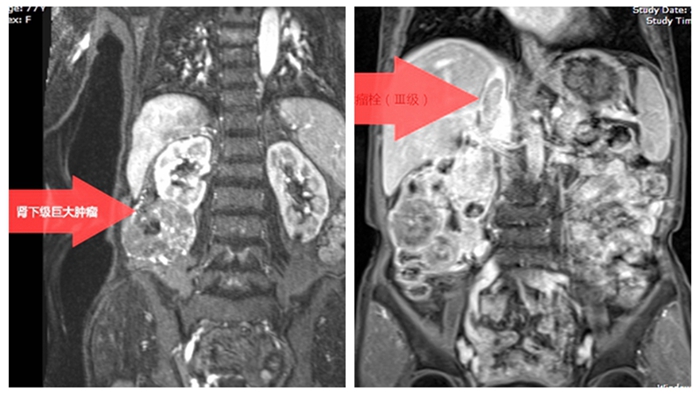

田奶奶家人慕名找到湘雅常德医院泌尿外科专顿金庚教授及团队,经过进一步检查,确定肿瘤位于右肾下端,最大直径达10厘米,同时形成长段静脉癌栓,相当于肿瘤沿右肾静脉进入下腔静脉内,癌栓分级为Ⅲ级瘤栓。而下腔静脉是下肢、部分盆腔和腹膜脏器的血液回流到心脏的主要通道。癌栓随时可能脱落,一旦癌栓脱落掉到心脏,进而跑到肺动脉,造成肺动脉栓塞,死亡率极高,抢救成功率非常小,可谓是“高危炸弹”。

静脉系统侵犯是局部进展性肾癌的特点之一,部分侵袭性较强的肿瘤在患侧肾静脉形成癌栓,继而沿着肾静脉生长,进入下腔静脉。右肾癌根治并腔静脉癌栓取出手术需要处理人体主干血管与十余根高血流量的血管,手术操作复杂、难度较大,如果术中操作稍有不慎,癌栓脱落便可以引起致死性的肺栓塞,因此,该手术是泌尿外科风险难度最大的手术。

传统的开放手术,需要在患者双侧腹部切口或横跨腹部的人字形大切口,下腔静脉与肾静脉后方的分支血管显露不佳,术中大出血与癌栓脱落的风险高。腹腔镜下可以用腹腔与腹膜后入路联合,在开放手术视野不可及的空间内从容操作,而且,放大6-10倍,更精准,减少对癌栓的碰触与牵扯。最终,经过充分的术前沟通,患者和家属决定进行腹腔镜下手术。